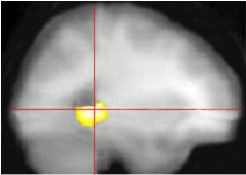

![]() |

The gray scale depicts averaged T1-weighted activity on MR. The color scale represents PET data at all voxels where perceived memory decline and metabolic decline over subsequent years (2) were significantly correlated (p<0.001). Images courtesy of Dr. Gary Small.